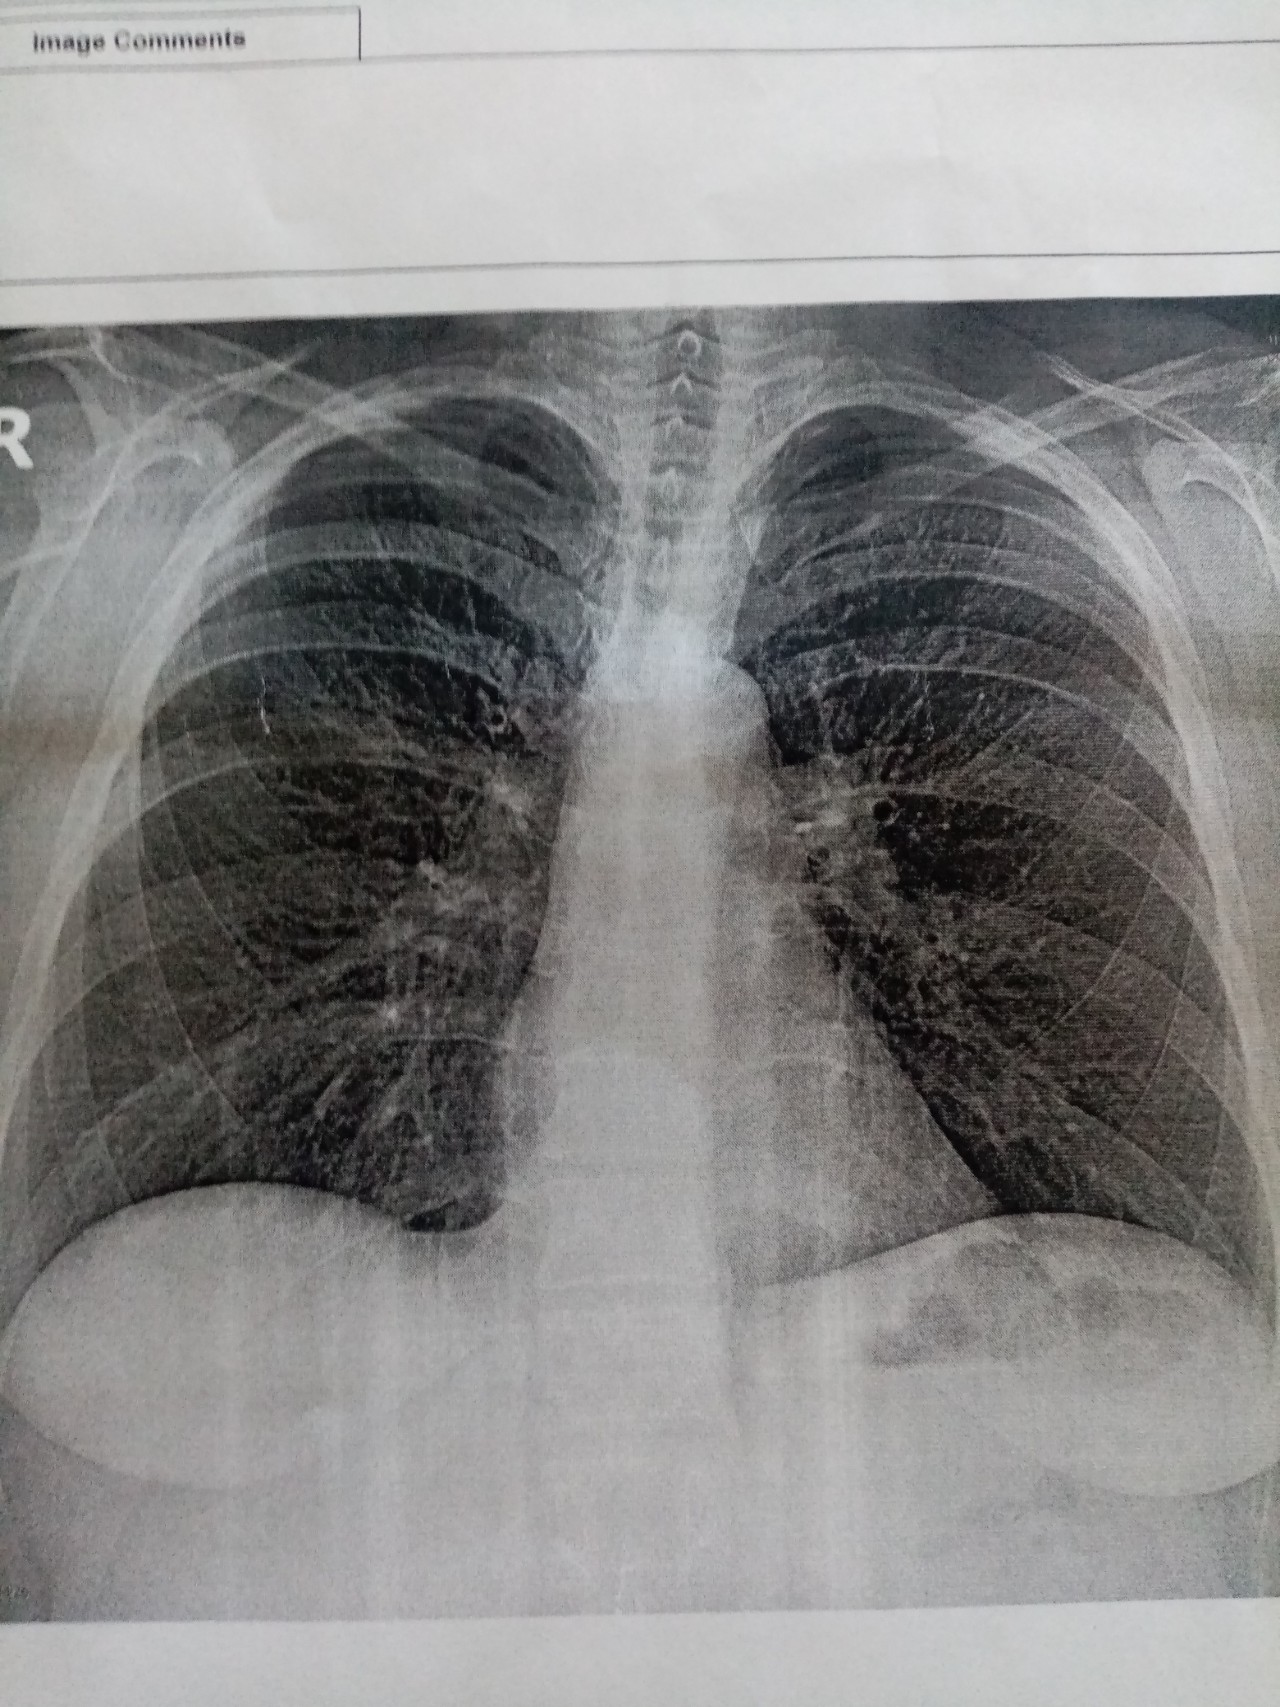

Что такое малоконтрастная рентгенограмма органов грудной клетки